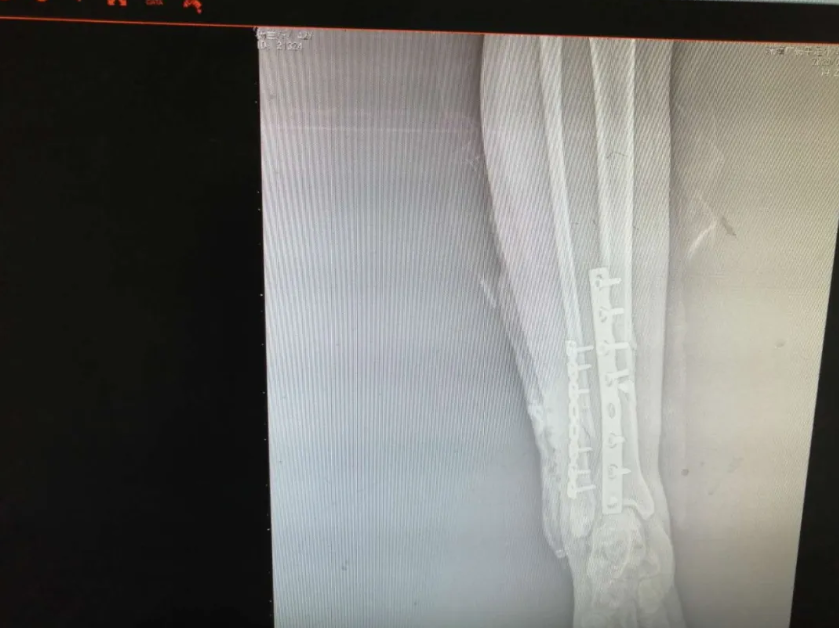

随后,医生根据杨女士的自身情况对她说明要等到患肢消肿后方可行手术,没消肿做手术的话会对术后伤口愈合不良,但考虑到其患肢自行消肿时间会比较长,所以建议予中药外敷以减轻肿胀和疼痛情况,杨女士表示接受治疗。中药外敷了几天后,效果明显,护士查房的时候问到患者感受,杨女士说第一天就感觉到效果了,明显没有之前那么痛了,于是在患肢消肿后就可以准备做手术了,谢业东主任给患者耐心讲解术前、术中、术后的注意事项以及术后的功能锻炼,杨女士在了解自己的治疗方案后,对手术更有信心了,在完善了术前相关检查后,手术于3月22日上午进行,行右胫腓骨开放复位内固定术,手术过程非常顺利,患者恢复良好,术后在医生护士的指导下进行康复功能锻炼,现已康复出院。

出院的时候,患者和家属不停地给医生道谢,表示对谢主任精湛医术的钦佩,同时一个劲的夸护士有责任感,工作中一丝不苟,态度又好。谢主任对患者的肯定表示感谢,同时叮嘱谢女士出院后患肢避免负重三个月,有不适症状的话随时复诊。